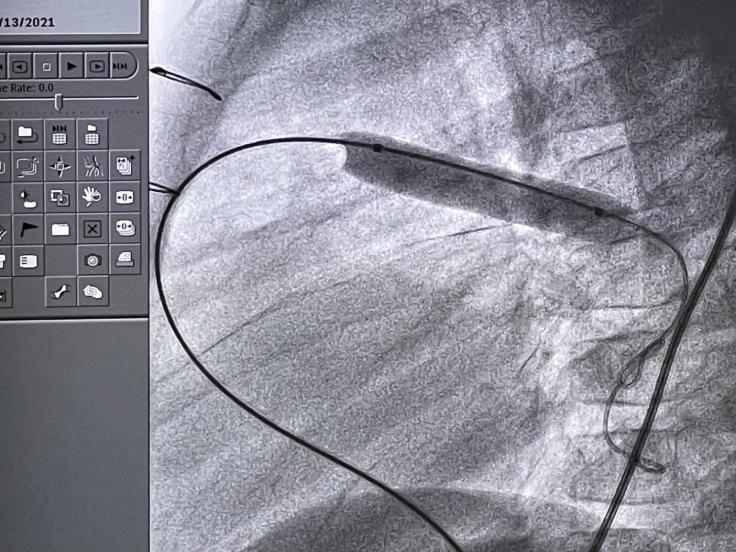

手动装载支架